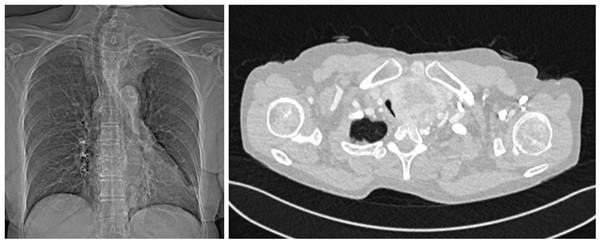

多单位多科室通力合作 胸外科精操作除沉疴

近日,我院胸外科应用4D打印气管外支架完成了一例高难度的手术,为患者解决了40多年未能解决的沉疴痼疾。 61岁的贺阿姨在十几岁时曾因为甲状腺疾病做过1次手术,遗憾的是因当时技术所限,肿瘤并未切除干净,此后的40余年,...